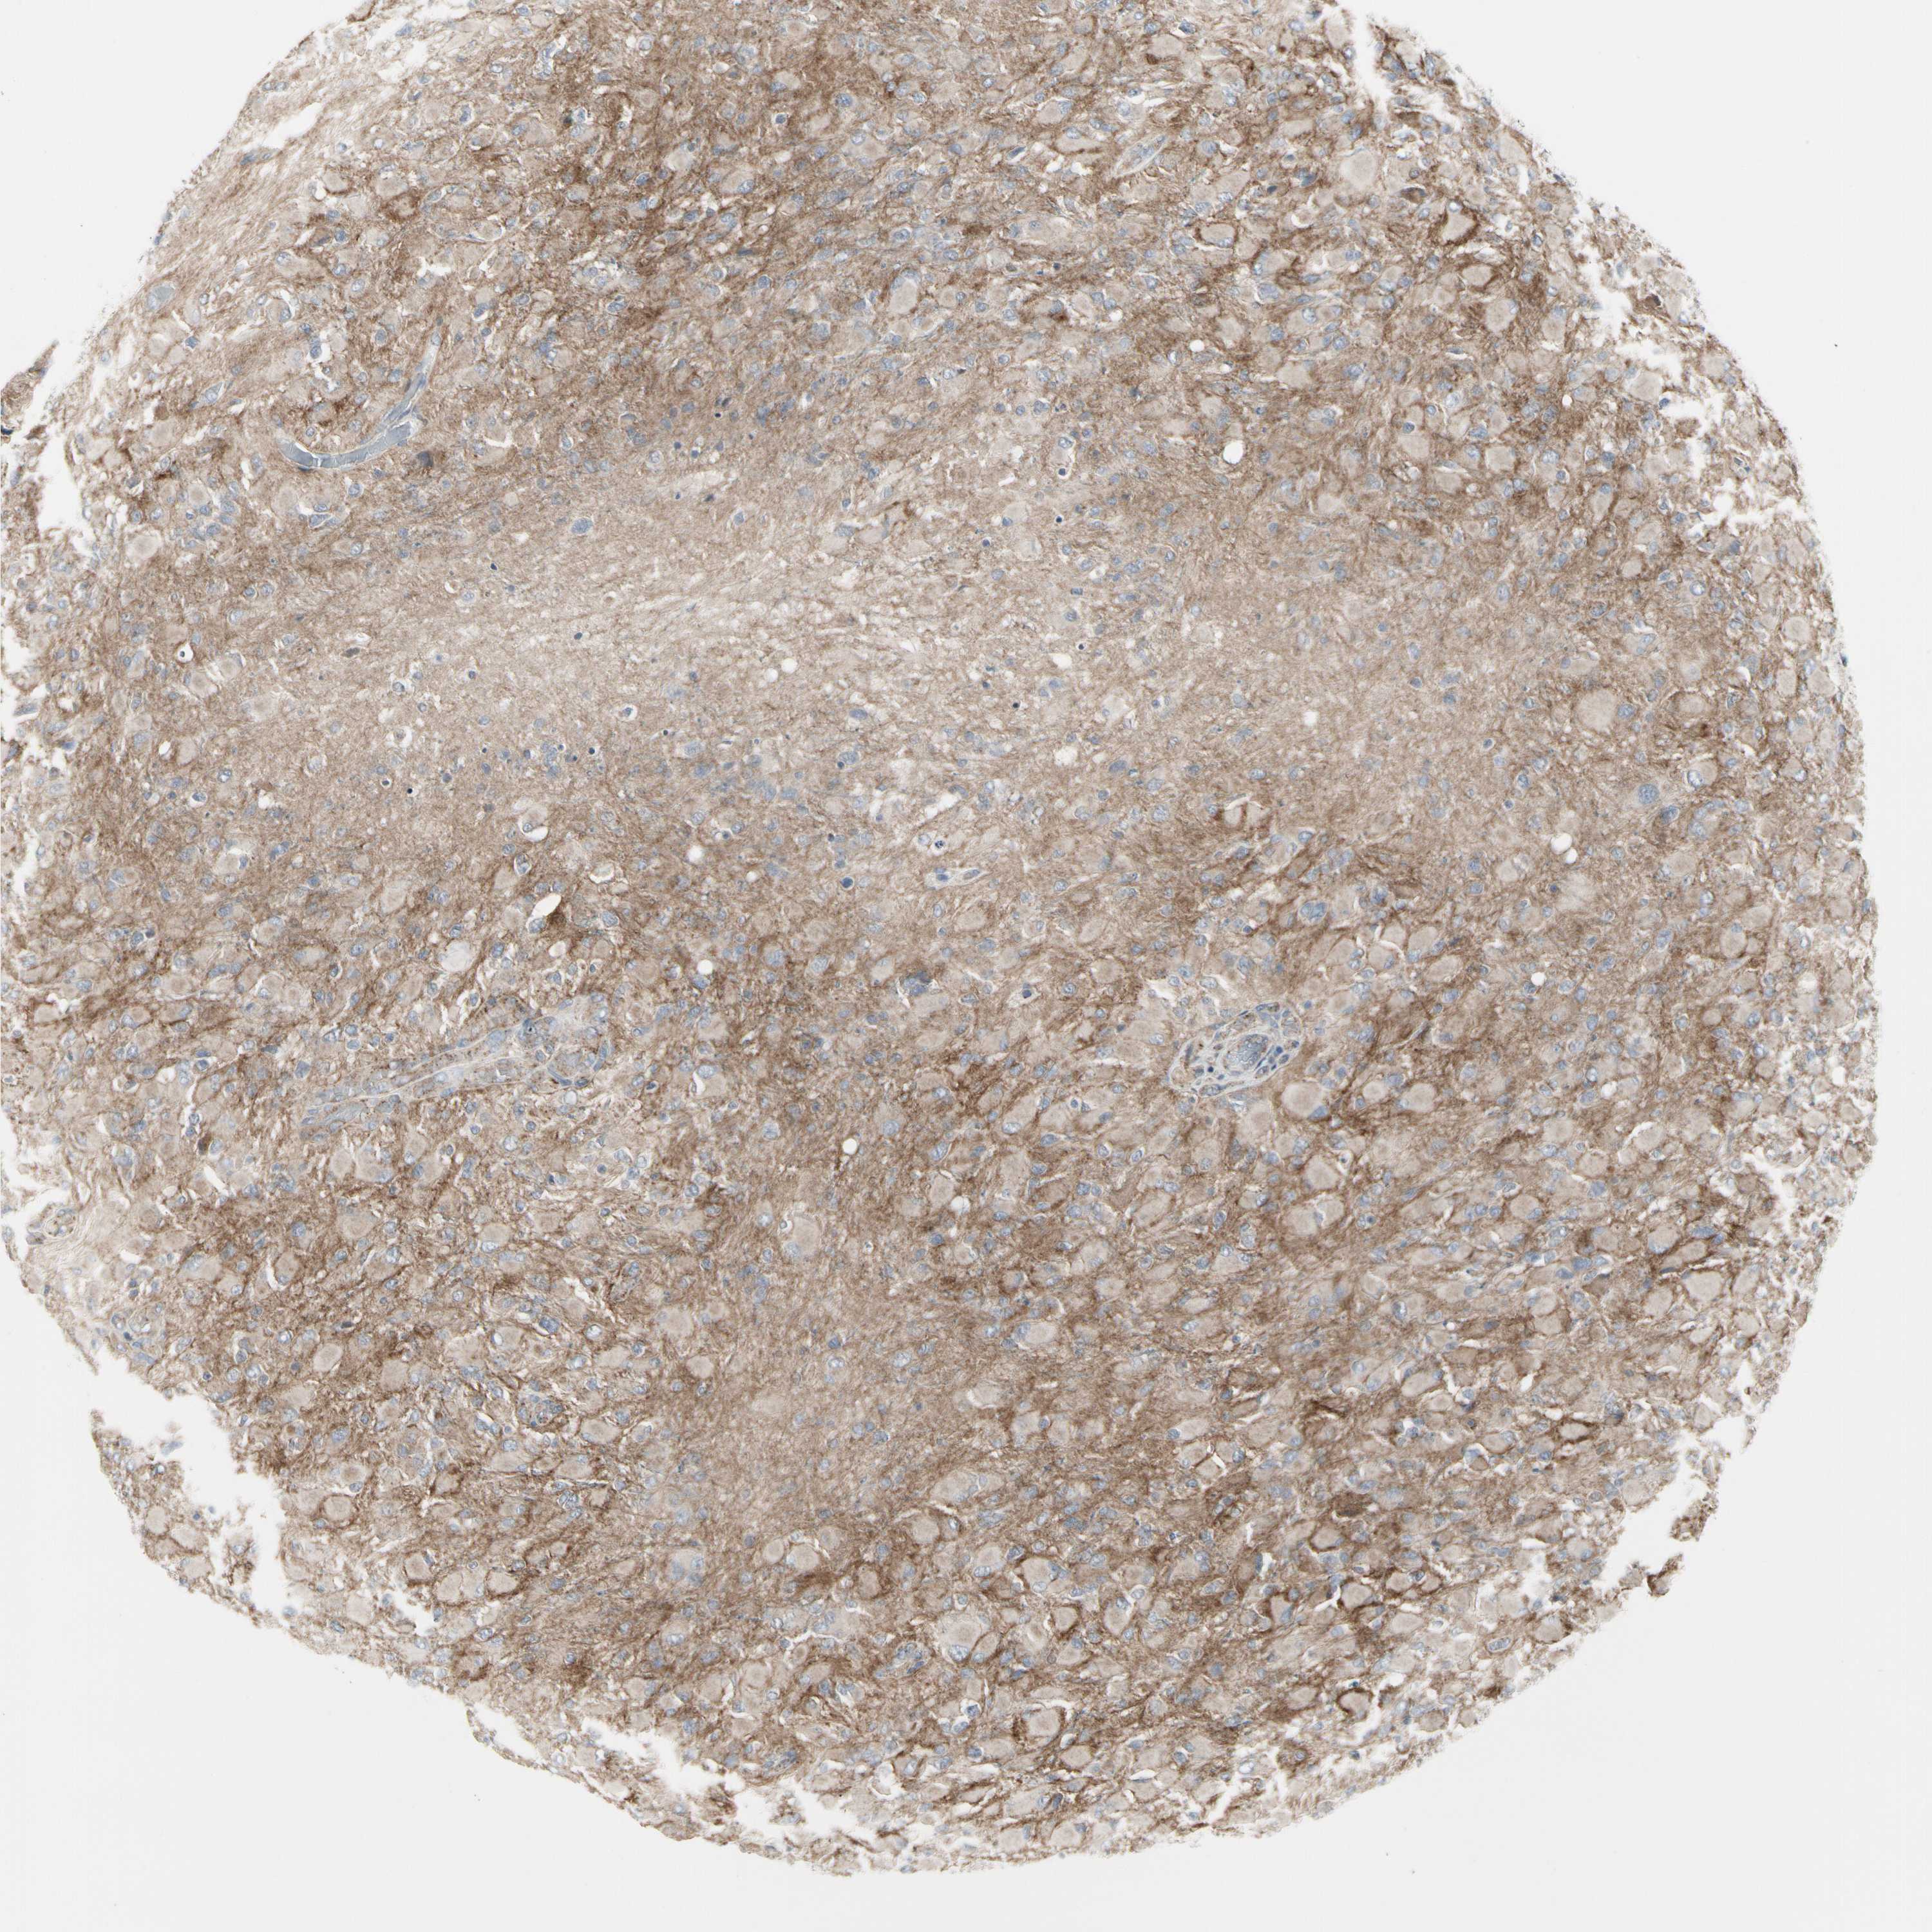

GLIOMA - Protein expressioni

A mouse-over function shows sample information and annotation data. Click on an image to view it in a full screen mode. Samples can be filtered based on level of antibody staining by selecting one or several of the following categories: high, medium, low and not detected. The assay and annotation is described here.

Note that samples used for immunohistochemistry by the Human Protein Atlas do not correspond to samples in the TCGA dataset.

Antibody stainingi

Antibody staining in the annotated cell types in the current human tissue is reported as not detected, low, medium, or high, based on conventional immunohistochemistry profiling in selected tissues. This score is based on the combination of the staining intensity and fraction of stained cells.

Each image is clickable and will lead to virtual microscopy that enables deeper exploration of all samples and also displays staining intensity scores, fraction scores and subcellular localization as well as patient and tissue information for each sample.

Antibody HPA008763

Antibody HPA028747

Antibody CAB019394

Staining

High

Medium

Low

Not detected

Intensity

Strong

Moderate

Weak

Negative

Quantity

>75%

75%-25%

<25%

None

Location

Nuclear

Cytoplasmic/membranous

Cytoplasmic/membranous,nuclear

Glioma, malignant, High grade

Glioma, malignant, Low grade